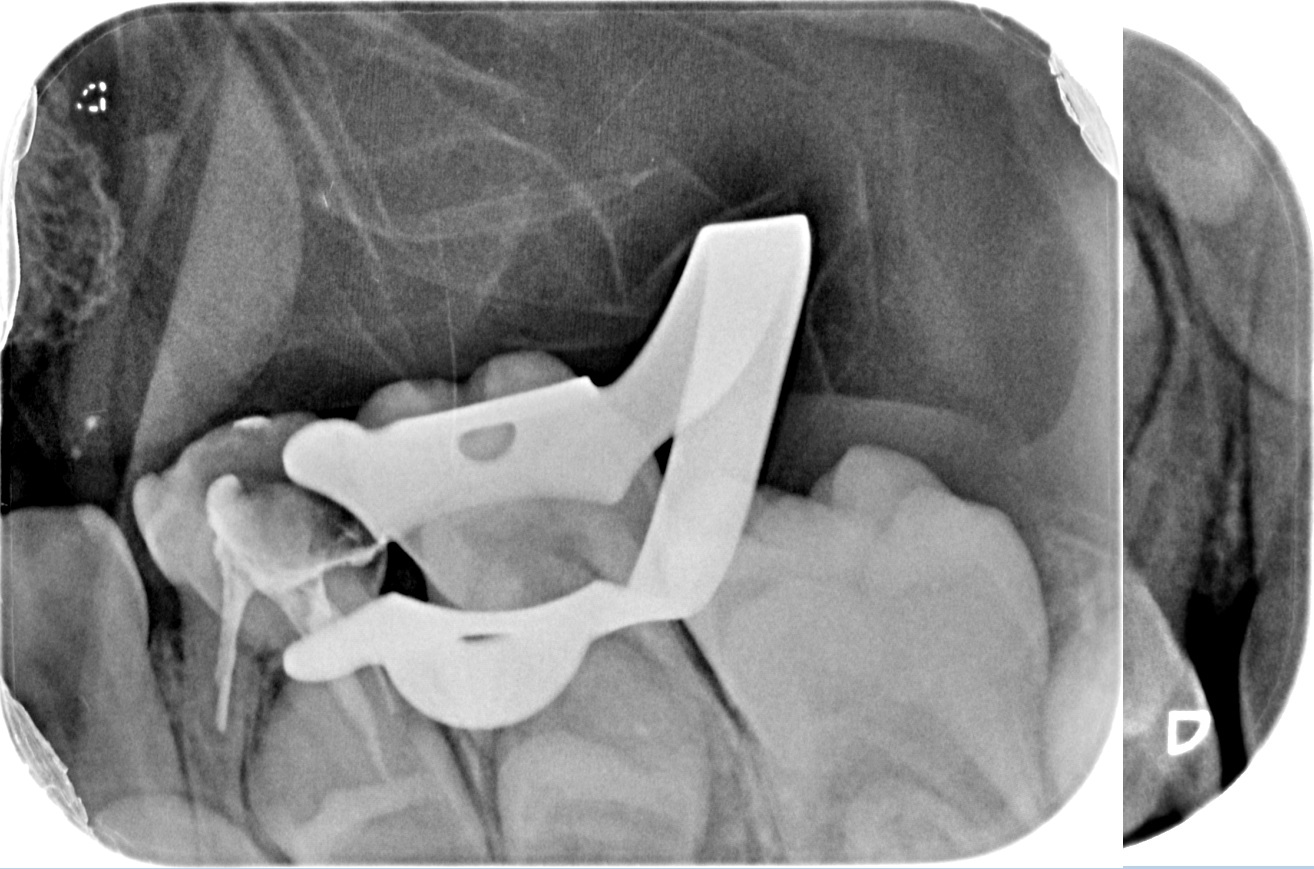

Our dentists perform root canal therapy every day. Complex anatomy and retreatments are routine. Each difficult case is planned by our senior clinician to ensure the right strategy from the start. - Microscope precision and isolation

Every procedure is performed under magnification with a rubber dam in place. Electronic length measurement (apex locator) ensures accuracy to the tip of the root. - Thorough cleaning and reliable sealing

We use rotary nickel-titanium instruments, activated irrigation for deep disinfection, and modern bioceramic sealers for a dense, long-lasting seal. - Targeted diagnostics

Under bright magnified light, a tiny opening is created and every canal located — even the hidden ones that often cause failures elsewhere. - Cleaning and shaping

The canals are shaped with flexible rotary files to create an ideal form for irrigation while preserving tooth strength. - Disinfection

We use activated solutions to eliminate bacteria and flush out microscopic debris, ensuring the system is clean throughout. - Sealing

The canals are filled with a stable, biocompatible material and sealed against future infection. - Immediate protection